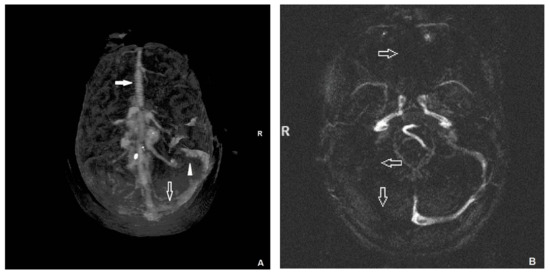

Bilateral Abducens Nerve Palsy Due to Extensive Cerebral Venous Sinus Thrombosis

2. Case Presentation